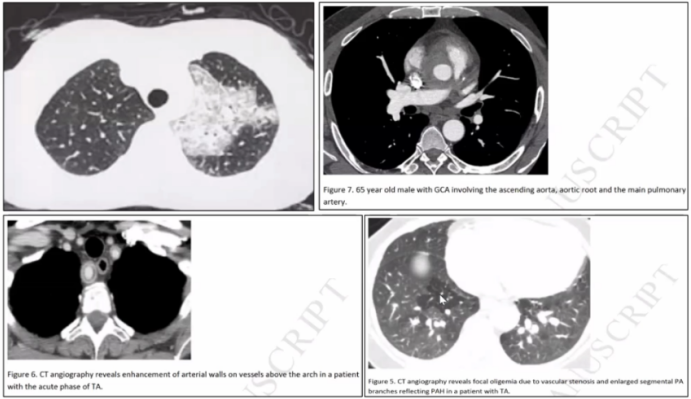

1. 大动脉炎肺内表现

大动脉炎肺受累最多见于血管,在增强CT上可见血管上有环状改变。巨细胞血管炎,主动脉根部的血管壁明显增厚[3]。Takayasu动脉炎的肺血管受累后,透过度明显减低。个别病例会出现弥漫性肺胞出血。

图片

大动脉炎合并呼吸衰竭的原因主要有:①肺动脉高压;②弥漫性肺泡出血,可能是侧支循环后导致动静脉瘘形成或动脉瘤破裂后出现的肺泡出血[4,5]